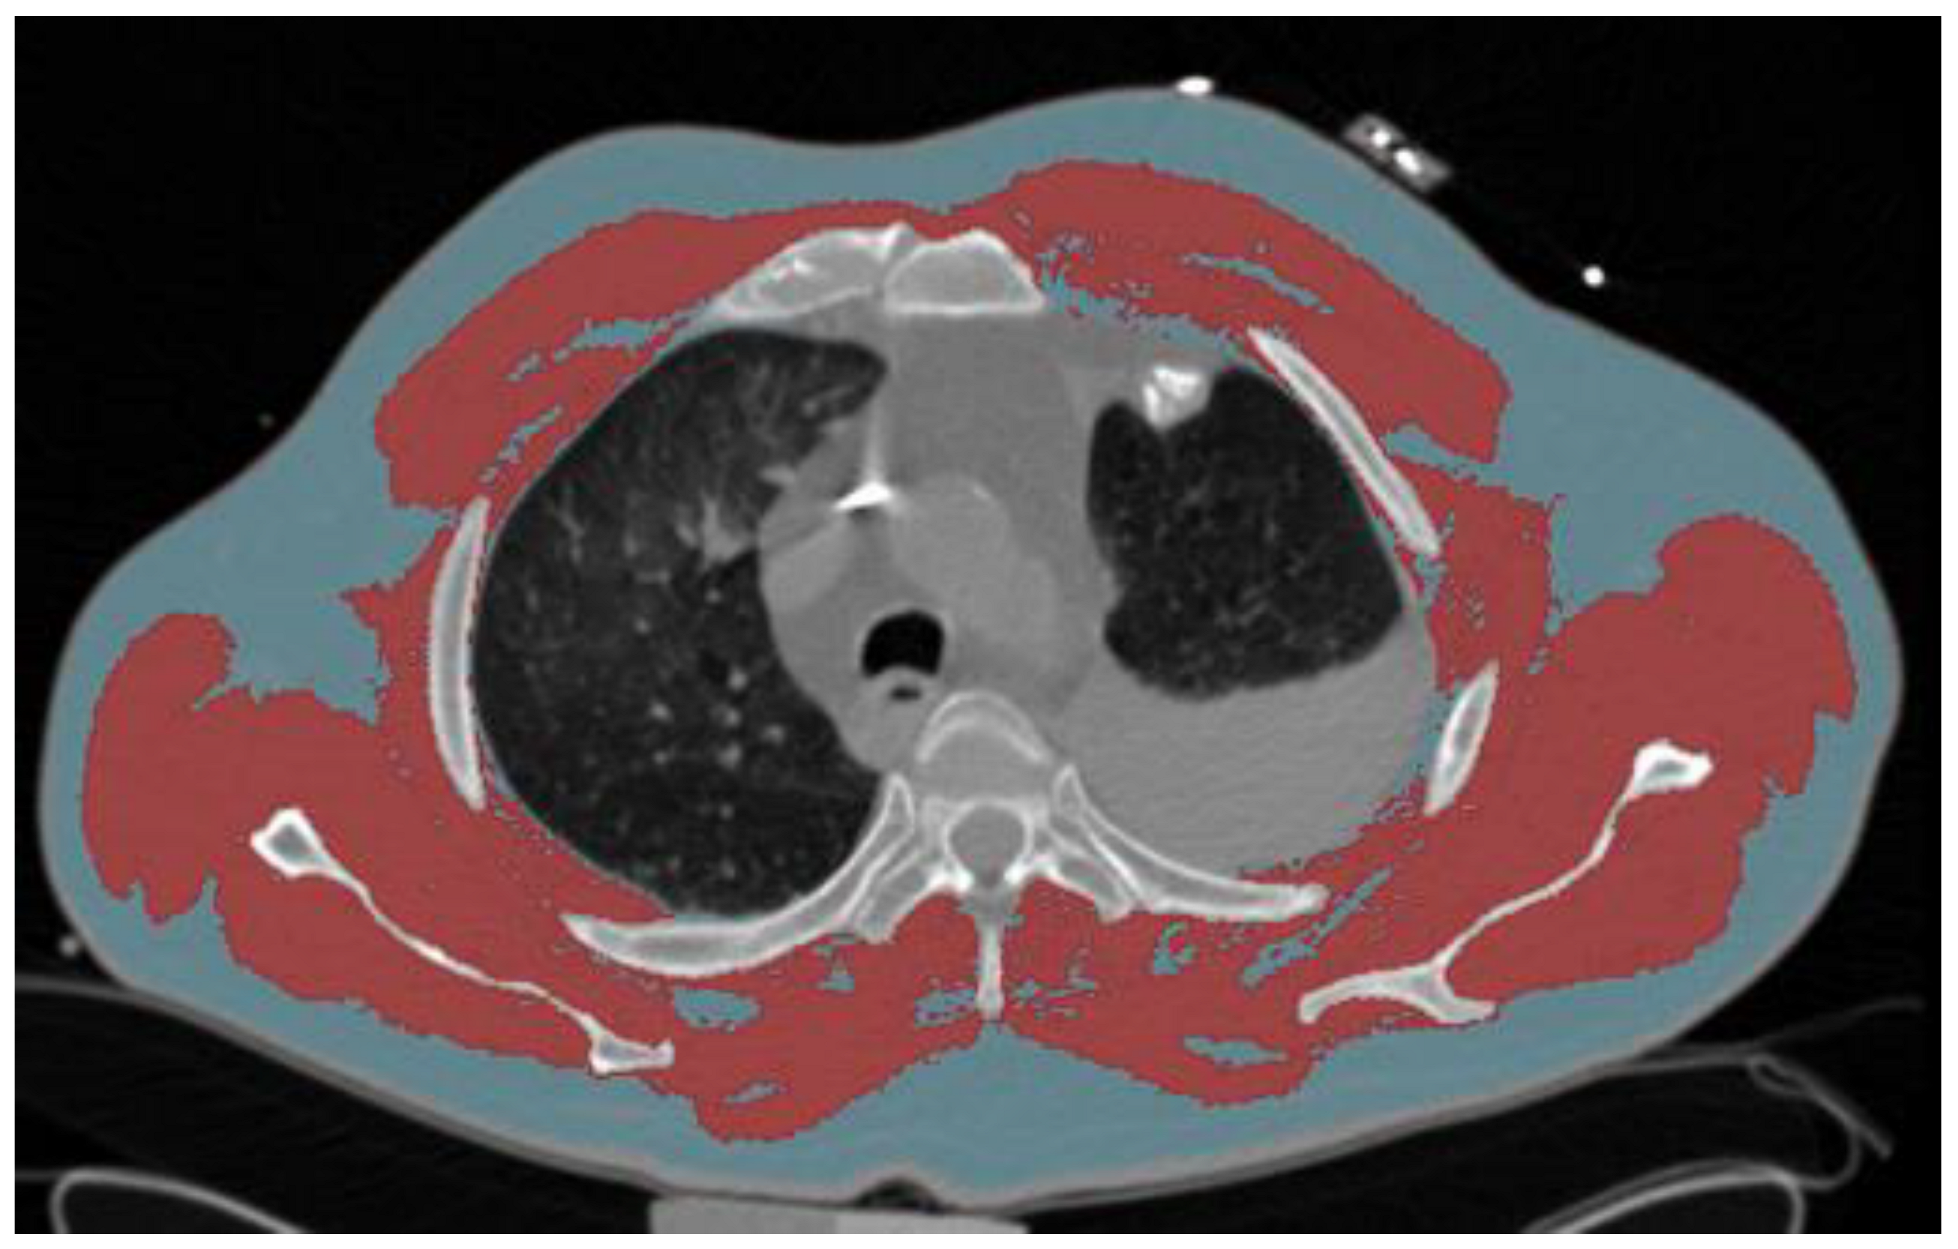

2.6. BC Analysis Using CT